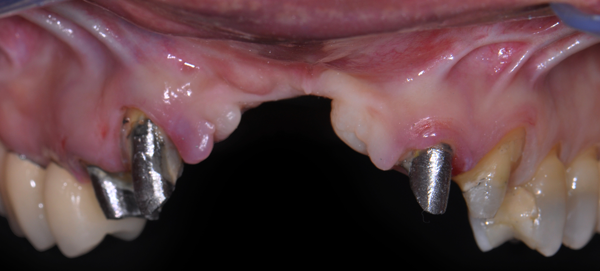

Entretanto, é de suma importância a correta e precisa abordagem cirúrgica, no que tange à incisão do rebordo alveolar. Nesse procedimento, foi realizada uma incisão “invertida”, que seria uma modificação da técnica de Kazanjian1. Uma incisão labial foi realizada perto do limite do vermelhão do lábio (Figuras 2 e 3), produzindo um retalho de base palatina, o que é indicado sempre que há necessidade de aumento substancial na altura do rebordo maxilar anterior (Figuras 4 e 5).

Foi utilizada uma membrana de politetrafl uoretileno denso (PTFE-d) reforçada com titânio (Cytoplast Ti250PS 20 mm x 25 mm, Osteogenics Biomedical) e osso heterógeno bovino (Lumina Porous, Critéria Biomateriais). O desenho do retalho invertido de base palatina (descrito anteriormente) foi escolhido para garantir fechamento após o procedimento de enxerto ósseo, apesar da dimensão aumentada da crista. Após o acesso ósseo, a membrana foi fixada com parafusos na região palatina (Figura 6) e o leito receptor foi preparado com penetrações múltiplas na cortical, usando uma pequena fresa (Figura 7).